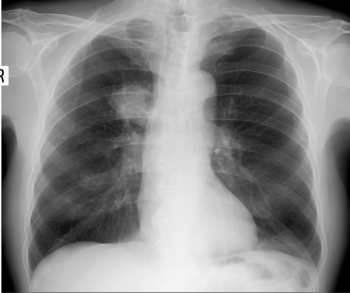

What is your diagnosis?